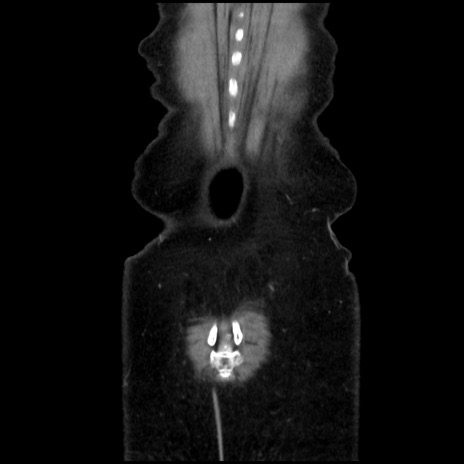

症例32(冠状断像)

症例

【症例】40歳代 女性

【主訴】上腹部痛、嘔気・嘔吐

【現病歴】約9時間前頃から急に上腹部痛、嘔気、嘔吐が出現。改善しないため救急要請。

【既往歴】子宮頚癌(広汎子宮全摘術、放射線療法)、腸閉塞

【身体所見】腹部:平坦、軟、腸雑音亢進、上腹部を中心に腹部全体に圧痛あり。

【データ】WBC 8400、CRP 0.03